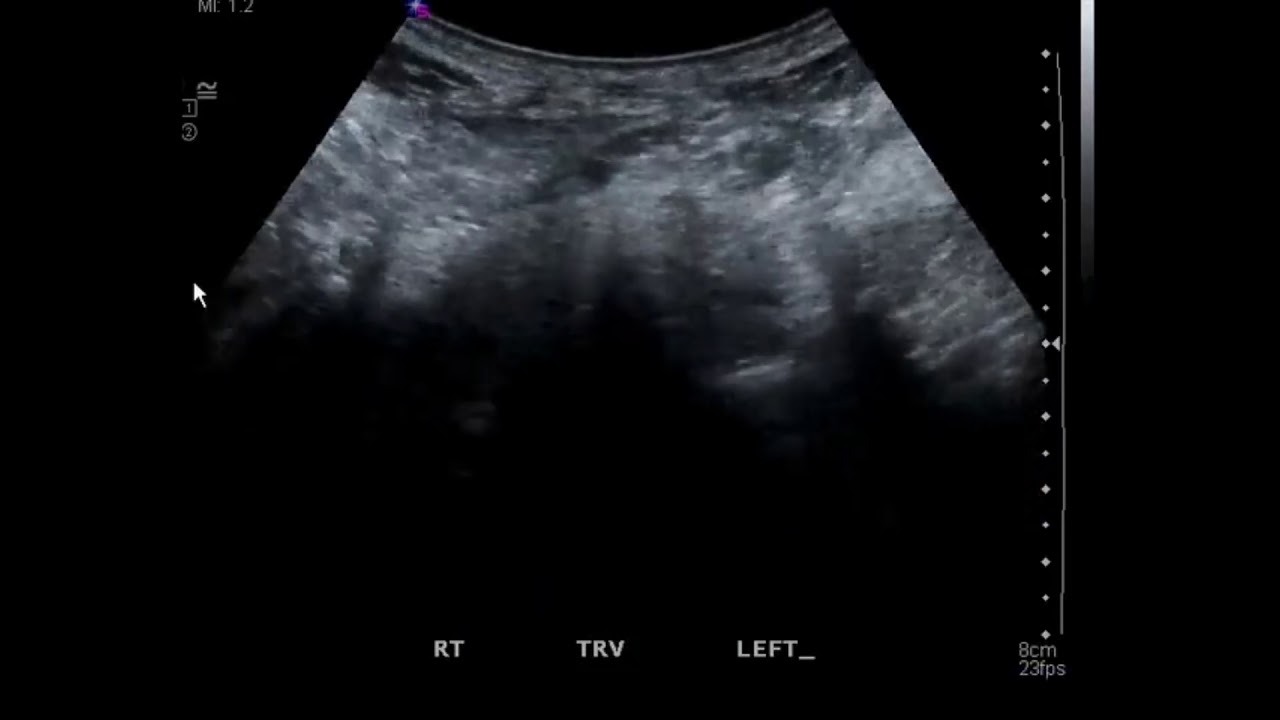

Le rein en fer à cheval est l'anomalie de fusion la plus fréquente, dans laquelle le parenchyme rénal de chaque côté du rachis est soudé au niveau du pôle controlatéral (habituellement le pôle inférieur); un isthme de parenchyme rénal ou de tissu fibreux se situe au niveau de la ligne médiane. Les uretères suivent un trajet.. Rein en fer à cheval. Le rein en fer à cheval correspond à la fusion des deux reins le plus souvent au niveau de leur pôle inférieur l'ensemble prenant une forme de U d'où cette appellation [1].. Définition. Il s'agit de l'anomalie de fusion la plus fréquente estimée à 0.25% de la population générale avec une prédominance masculine (2/1) [2]. Il peut être isolé ou s'intégrer.

Introduction. Le rein en fer à cheval est une anomalie urologique congénitale fréquente. Ses complications les plus fréquentes sont les infections urinaires, les lithiases et l'hydronéphrose. Par contre, la survenue de néphropathies glomérulaires est rare. Nous rapportons un cas de syndrome néphrotique survenu chez un patient ayant un.. Urétérorénoscopie souple-laser et calculs sur rein en fer à cheval. Dans notre étude, 73% des patients avaient au moins un cal-cul dans le calice inférieur, où l'angle de travail complique l'intervention et réduit la chance d'éliminer spontanément les petits fragments. Miller et al. dans leur série de NLPC sur rein en fer à.